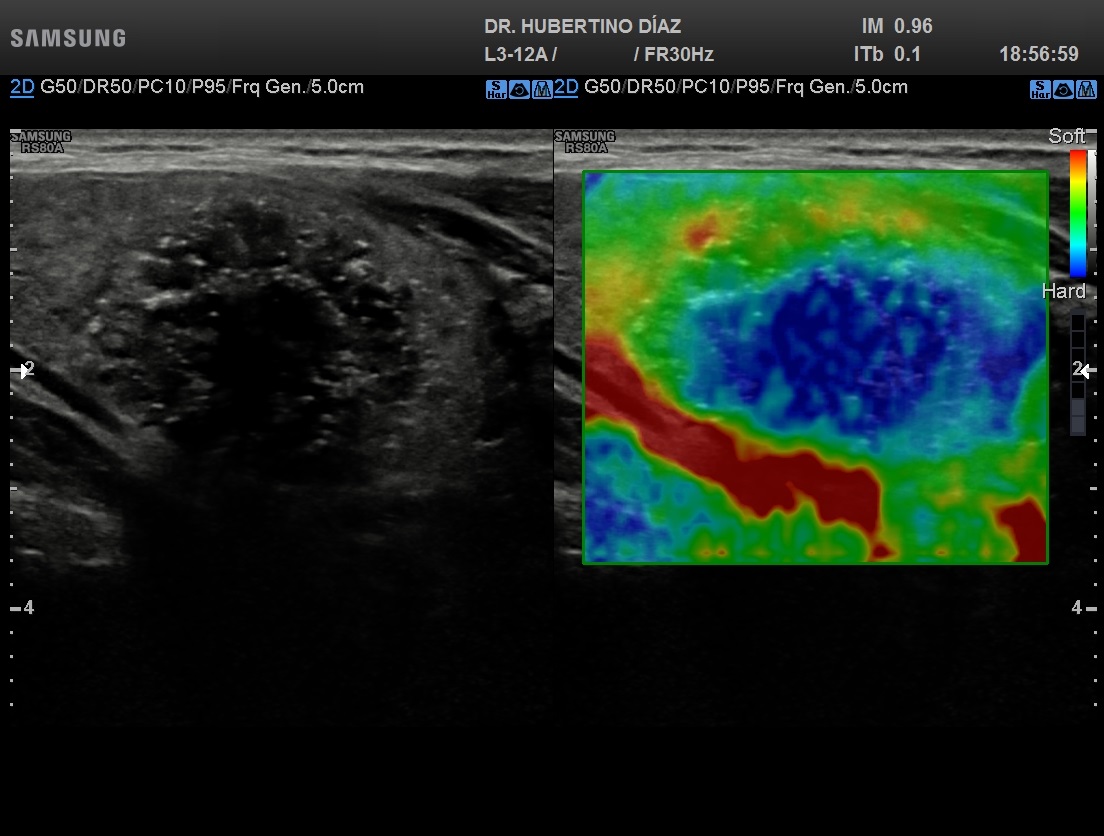

ELASTOGRAFÍA DE TIROIDES

La elastografía es una técnica que se realiza junto con la e...